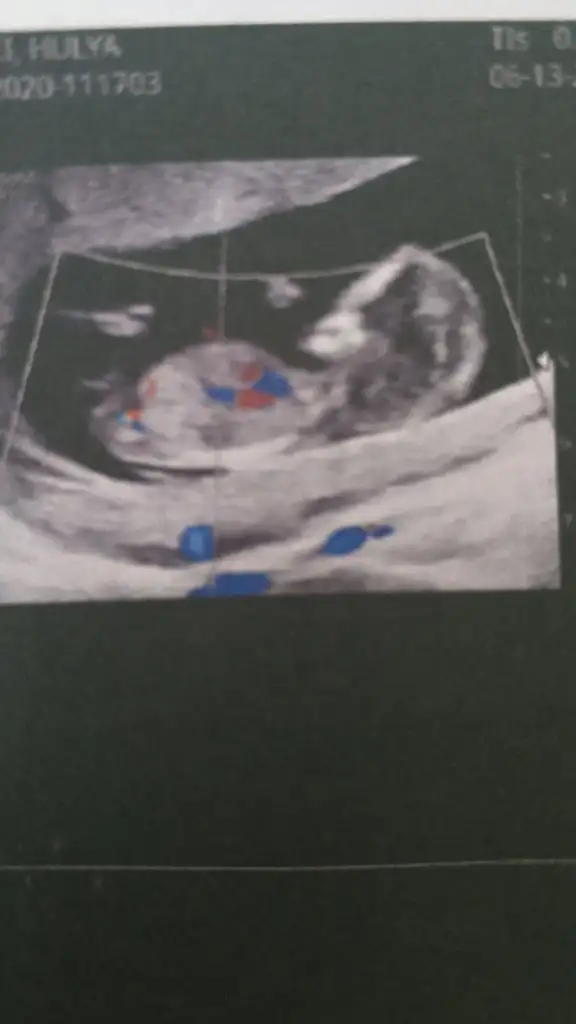

Kız gibi geldi nubu tam karşıya bakıyor ama ben oyumu kıza kullandım

Allah'ım ağzın bal yesin kızKız gibi geldi nubu tam karşıya bakıyor ama ben oyumu kıza kullandım

Hayırlısı olsun cnmAllah'ım ağzın bal yesin kızsen ne dersen tutuyor zaten gerçi kız olsun erkek olsun önemli değil sağlıklı olsunda ilk bebeğim erkek olunca gönlümde de kız yatmıyor değildi hani doktor söylemedi 2 hafta sonra gel bidaha bakalım dedi bakalım

Ay hadi İnşallah bakalım hayırlısı Rabbimdenben de ki diyorum benim usg ye benziyor inşallah kızdır ikimizin kide canımsonbuse